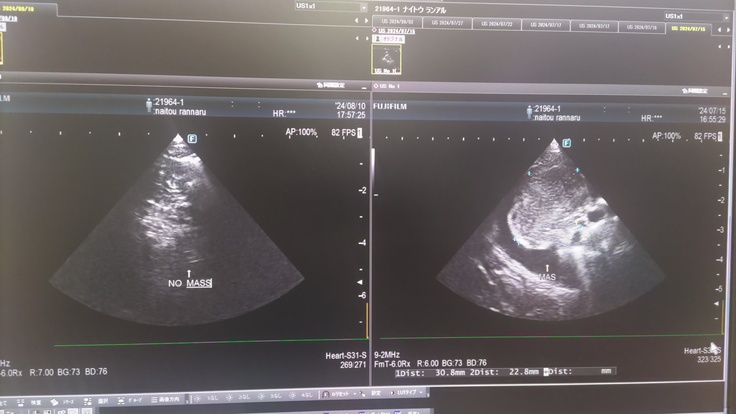

胸部 約3cm×2cmの腫瘍 こちらも見づらいですが、薄く十字点線で示しているのが腫瘍です

↓治療のおかげで腫瘍がほとんどなくなりました。

左の写真が現在の胸の腫瘍(ほぼ無し)、

右の写真が7/15の時の腫瘍(3cm×2cm)